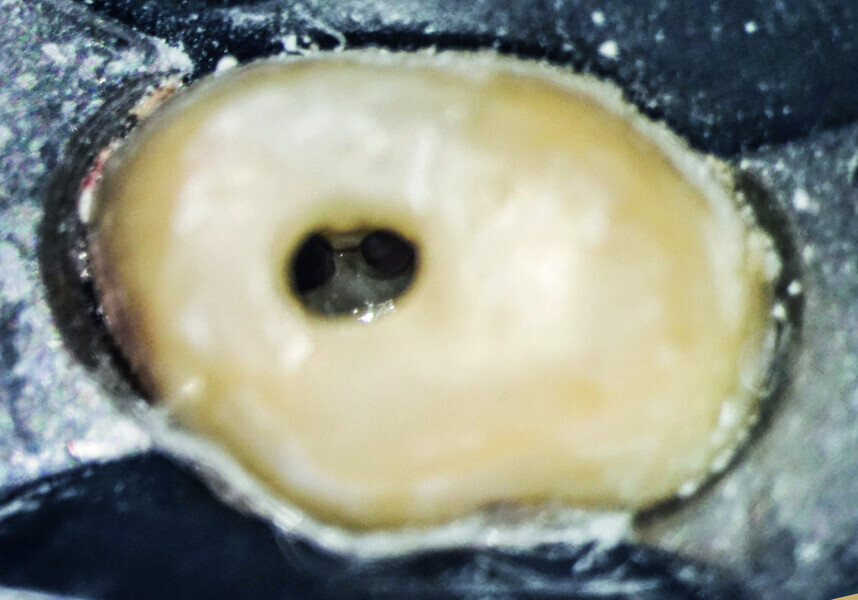

Minimally invasive root canal shaping—A new protocol